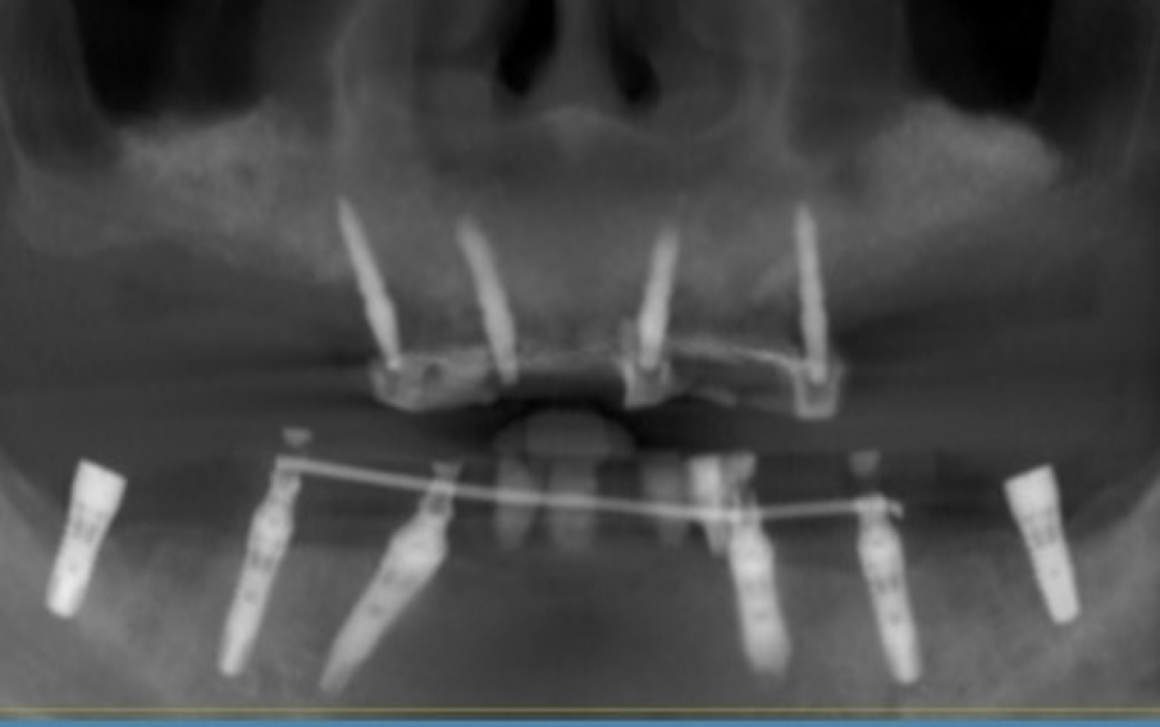

Тотальная реабилитация

Проблема: Отсутствие зубов